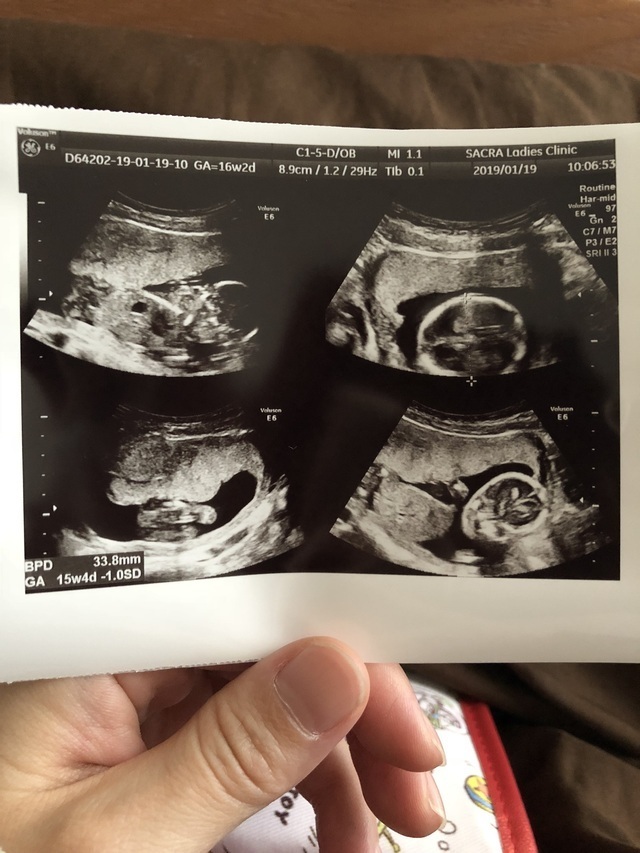

16週2日(16w2d・男の子)|Sumimamen さん(38歳)

エコー写真撮影時のエピソード:

横向いて寝そべるかたちで「どーもすみません」って林家三平師匠のようにおでこに手を当ててます。小鼻と目がはっきりとわかって人らしく写った初めての一枚。

写真を見ると大きくなるお腹を見る目も少し変わって中に子どもがいる実感が湧きました。